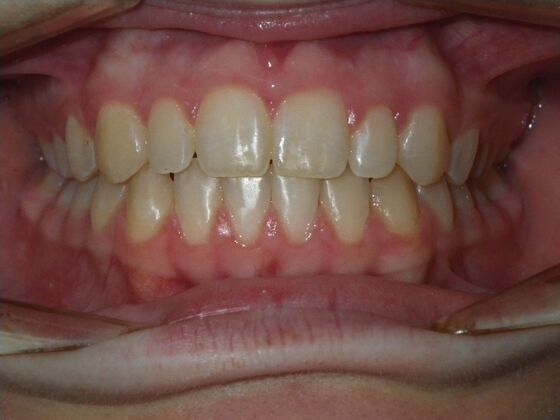

Orthodontics: Case 10

Description

This case presents with a dental midline discrepancy. The upper incisors are tipped toward the palate, which prevents the lower incisors from establishing proper arch form. The upper right molar has drifted forward, causing the upper midline to be skewed to her left. By distalizing the upper left molar, we can correct the midline discrepancy. Lastly, both upper and lower arches need expansion. All of this was completed with conventional straight wire appliances within 2 years.